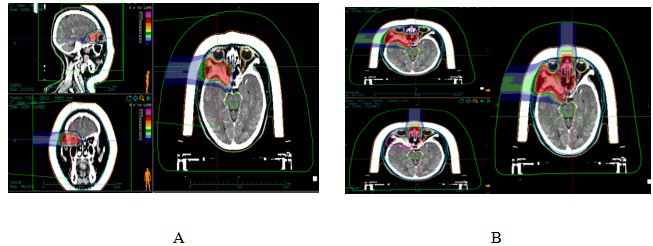

图1泪囊鳞癌CIRT治疗剂量分布图

Figure 1 CIRT dose distribution in patients with dacryocystosquamous cell carcinoma

Note: Figure 1A: One course CIRT dose distribution. Figure 1B: Two course CIRT dose distribution

图2 泪囊鳞癌患者VMAT计划及碳离子计划剂量分布图

Figure 2 VMAT plan and carbon ion plan dose distribution in patients with dacryocystosquamous cell carcinoma

Note: Figure 2A: VMAT plan dose distribution in patients with dacryocystosquamous cell carcinoma. Figure 2B: Carbon ion plan dose distribution in patients with dacryocystosquamous cell carcinoma.